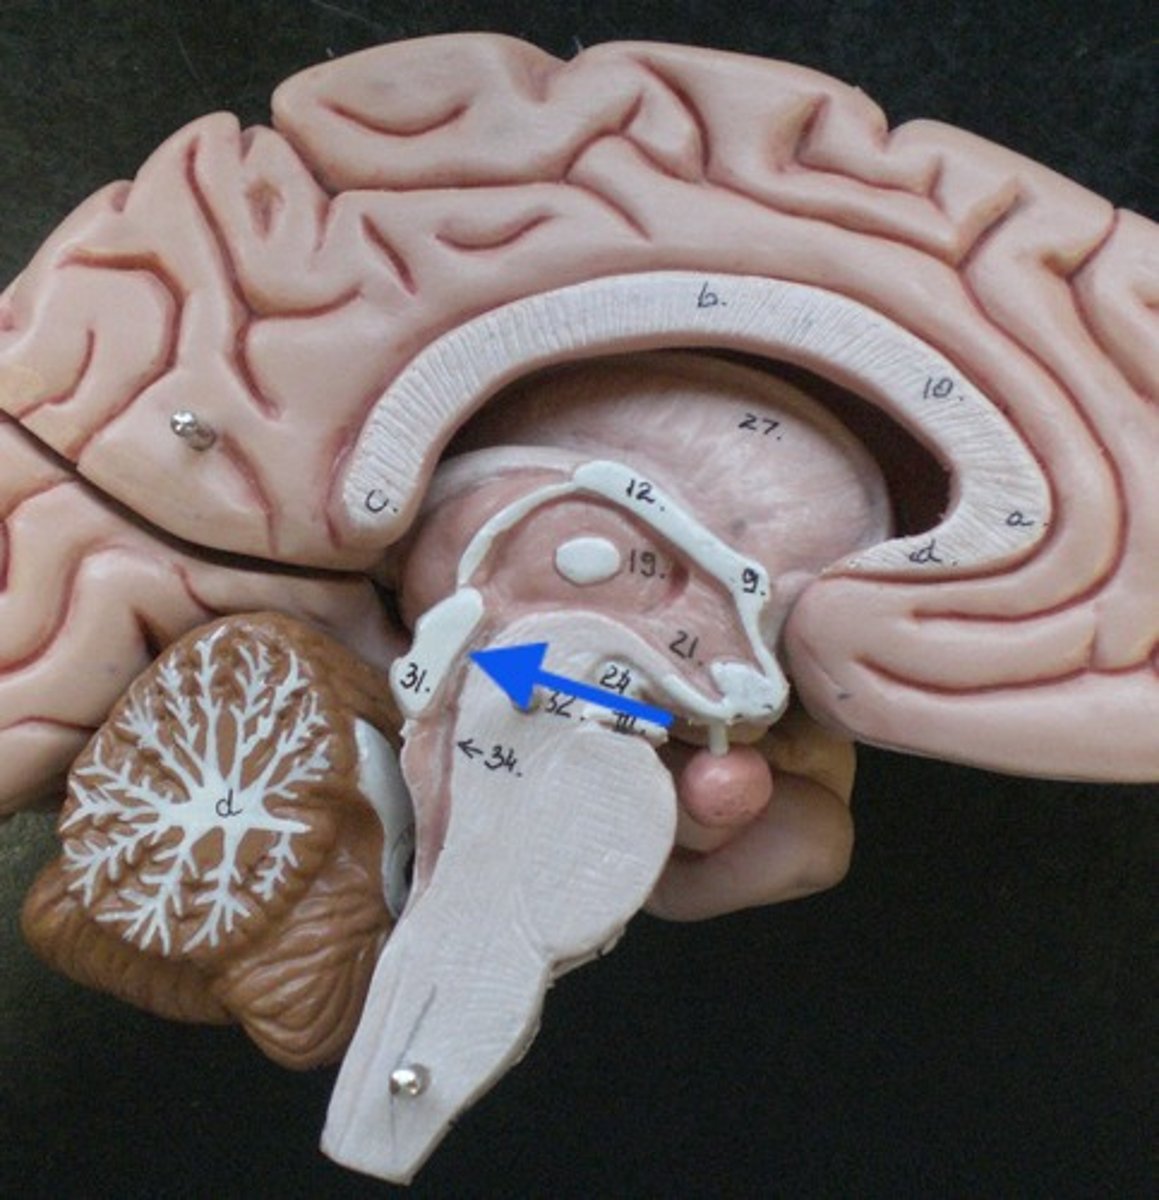

What anatomical aspect of the 4th ventricle is considered its floor?

refers to the floor of the 4th ventricle

rhomboid fossa

What forms the floor (rhomboid fossa) of the 4th ventricle?

dorsal surfaces of pons tegmentum and open medulla

obex

vertical groove running in the floor of the 4th ventricle that separates it into right and left halves

dorsal median sulcus

vertical groove lateral to the dorsal median sulcus of the 4th ventricle

**same one that separated the alar and dorsal plates in the neural tube during development

sulcus limitans

refers to most of the floor of the 4th ventricle lateral to the sulcus limitans

**namesake nuclei are here

vestibular area

triangular region located in the caudal portion of the rhomboid fossa of the 4th ventricle, where the dorsal motor nucleus of CN X is

vagal trigone

triangular region located most medially in the caudal portion of the rhomboid fossa of the 4th ventricle, where the CN XII nucleus is

hypoglossal trigone

part of the 4th ventricle superior to the vagal and hypoglossal trigones (still medial to the sulcus limitans)

medial eminence

small bump located in the caudal portion of the medial eminence which forms from the motor fibers of CN VII as they wind around the underlying CN VI nucleus

facial colliculus

pigmented area that looks blue near the superior aspect of the sulcus limitans; cluster of noradrenergic cells

locus ceruleus

fibers that run horizontally in the central region of the rhomboid fossa of the 4th ventricle

stria medullares

area that helps to make the walls of the obex and is thought to be the "vomit trigger"

area postrema

What forms the superior portion of the roof of the 4th ventricle? (A)

superior cerebellar peduncles

inverted V shaped interval between the superior cerebellar peduncles that is filled by a thin layer of white matter

superior medullary velum

lower portion of the roof of the 4th ventricle formed by a thin layer of pia mater and ependymal cells

inferior medullary velum